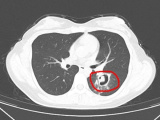

Trước diễn biến bất thường, bệnh viện địa phương chuyển bệnh nhân đến khoa da liễu của bệnh viện tuyến trên. Khi tiếp nhận, bác sĩ ghi nhận vùng đùi trong bên phải xuất hiện các mảng đỏ, bầm tím và nhiều bọng nước lớn.

Sau khi thăm khám, nhóm bác sĩ chẩn đoán bệnh nhân bị hoại tử mô cục bộ và nhiễm độc toàn thân do nọc độc nhện gây ra. Người bệnh sau đó được chuyển vào phòng điều trị để giải độc và theo dõi.